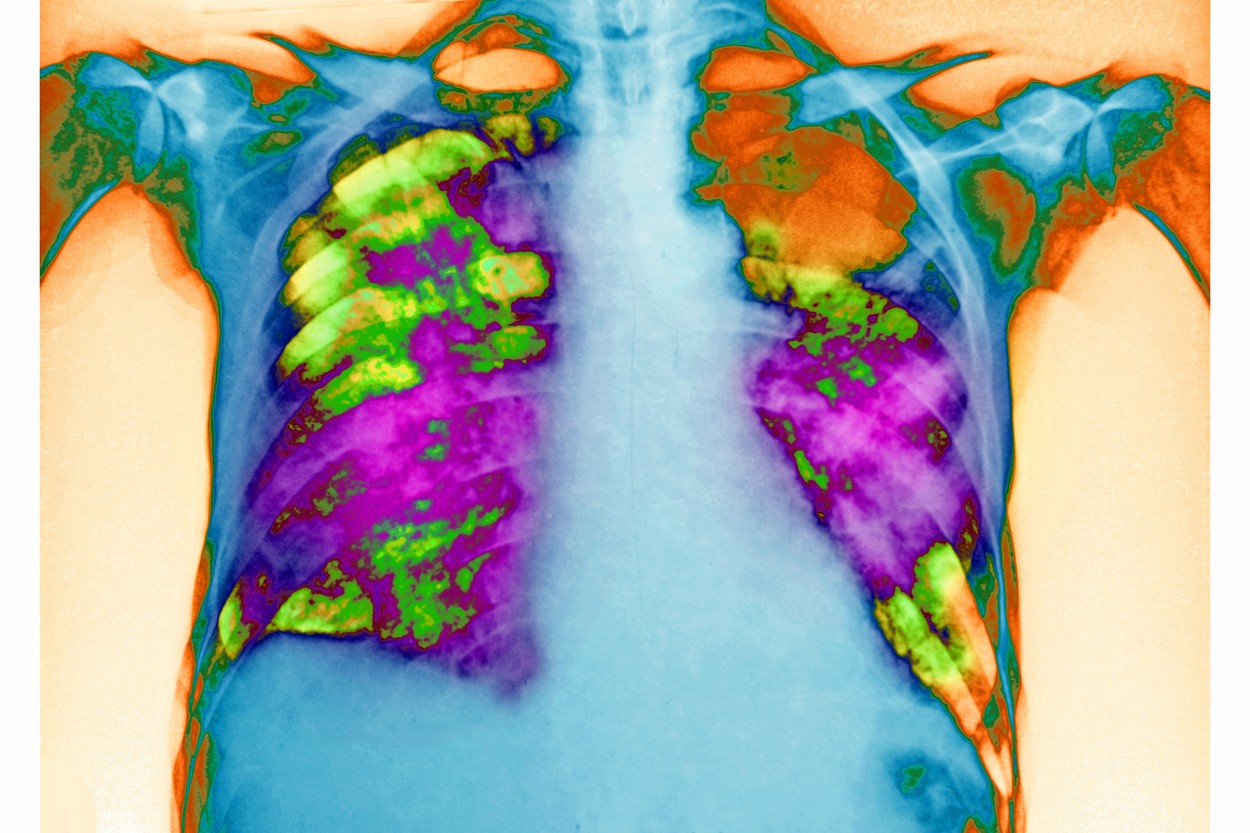

Pneumonija kao infekcija dišnog sustava, je upalno stanje koje zahvaća zračne vrećice u plućima, često uzrokovano infekcijama poput bakterija, virusa ili gljivica.

To dovodi do punjenja zračnih vrećica gnojem ili drugim tekućinama, što dovodi do simptoma poput kašlja, groznice i otežanog disanja. Pneumonija može varirati od blage do teške i može zahtijevati medicinsku intervenciju, osobito u osjetljivoj populaciji, piše Times of India.

Pravovremena dijagnoza i liječenje ključni su za potpuni oporavak i sprječavanje komplikacija.